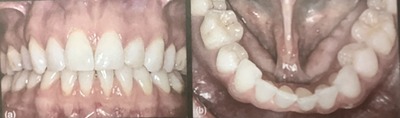

骨隆起、骨の出っ張りが下顎にあった。

全然詰めたものも無くて、キレイ。

歯ぐきも良い感じ。

レントゲンで影のあった下の前歯、2本とも電気と温度刺激にしみた。

歯周ポケットも浅くて、その周りの歯にも異常は見つからない。